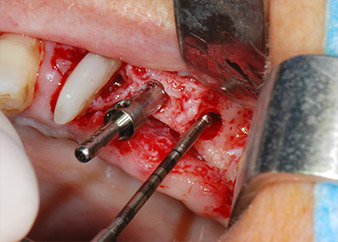

Implant beds were prepared at sites 25 and 26 with rotary instruments, used in a contra-angle handpiece with a 20 : 1 transmission ratio with an updated powerful implant motor (Implantmed, W&H) (Fig. 8).

The final preparation next to the sinus was again carried out with a piezoelectric instrument (Piezomed, insert S2).

Prior to implant placement, and following verification of an intact Schneiderian membrane (Fig. 9), the internal sinus floor was augmented at both implant sites by means of xenogeneic bone substitute material (Bio-Oss, Geistlich Biomaterials) (Fig. 10).

integrity of the sinus membrane

Fig. 9: After implant bed preparation at site 26, the integrity of the sinus membrane was checked with a ball-ended CPITN periodontal probe.

CPITN-probe

Fig. 10: Introduction of xenogeneic bone substitute material into the implant osteotomy for internal sinus augmentation. The material was carefully condensed in an apical direction with the ball-ended CPITN probe (not shown).